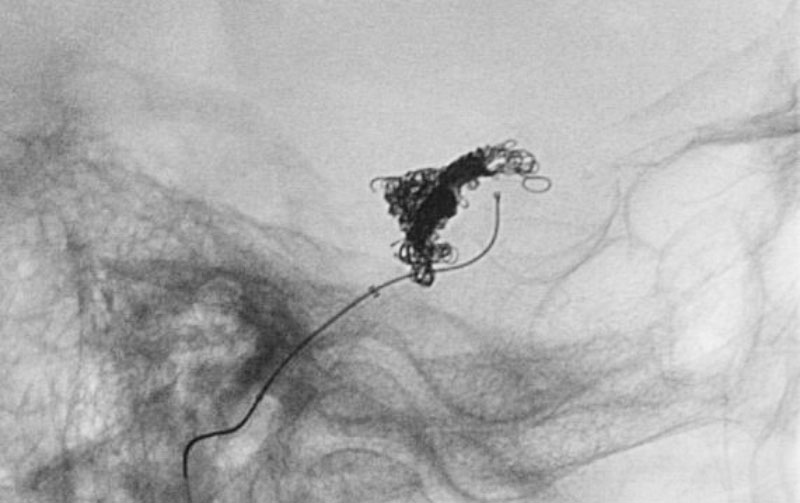

No.1591 手術中

No.1591 手術後

硬膜動静脈瘻

50代

救急外来